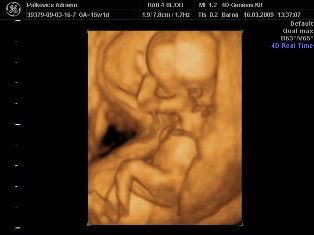

Uh képet is szívesen raknék fel, de hogyis??

Na megpróbálom...